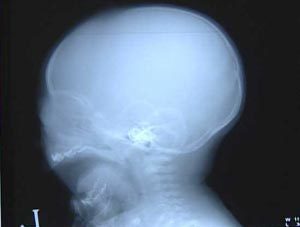

‘새로운 흐름-건강은 자궁에서 시작된다’ 편. ‘자궁 속 환경’(태내 환경)이 태아의 건강에 미치는 영향을 조명한다. 출생할 때 몸무게 2.5kg 이하의 저 체중아는 비만과 당뇨, 심장질환, 정신질환의 발병률이 높다. 각종 질병을 근본적으로 막기 위한 이상적 태내 환경도 진단한다.